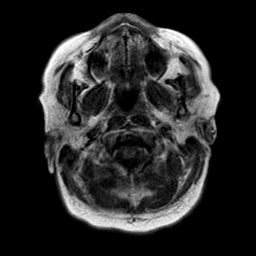

Cerebral hemorrhage, MR Study mr-t1 -- Slice #2

[Home][Help][Clinical] Slice 2